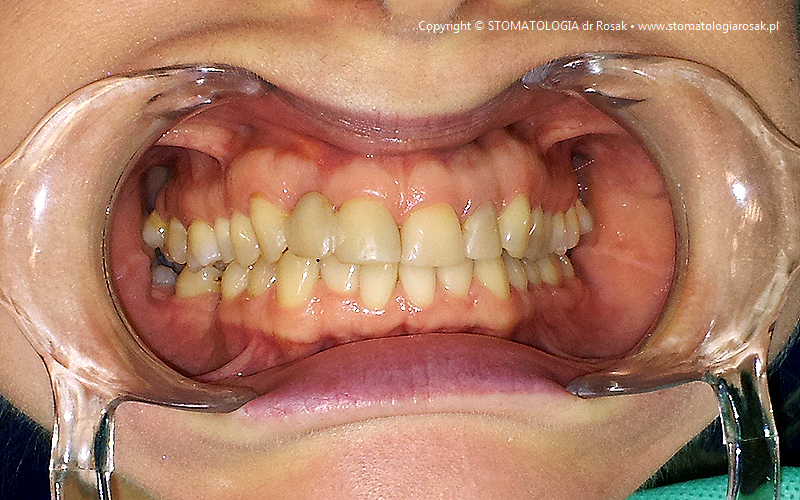

2. Pacjent z licznymi wypełnieniami (plombami), zgryzem głebokim, zaburzona estetyka

i funkcja układu narządu żucia (diastema).

| 2a. Pacjentka przed leczeniem |

2b. Gotowe mosty pełnoceramiczne

na podbudowie cyrkonowej |

2c. Gotowe mosty i korony pełnoceramiczne

2d. Gotowa praca stała - korony pełnoceramiczne